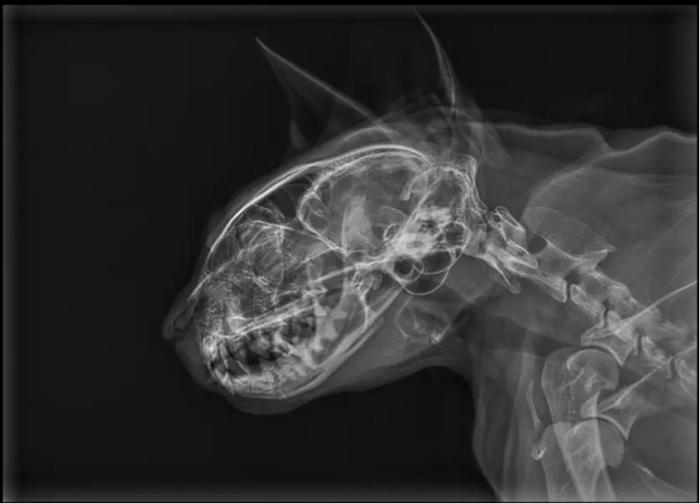

Las radiografías de cráneo pueden ser sugerentes de estenosis nasofaríngea, observándose opacidad de tejido blando dentro de la nasofaringe dorsal, y con frecuencia una desviación dorsal o deformación del paladar blando en el sitio de la estenosis4.

Ante la sospecha de una alteración de vías altas compatible con estenosis o pólipo nasofaríngeo, se realizó una radiografía de cráneo, en la cual se mostraba una alteración en la región nasofaríngea, a la altura de la zona de proyección de las coanas (Figura 2-3), compatible con una estenosis nasofaríngea o imperforación nasofaríngea.

En la radiografía de cráneo, se observó alteración en la región nasofaríngea, a la altura de la zona de proyección de las coanas, compatible con una estenosis o imperforación nasofaríngea.